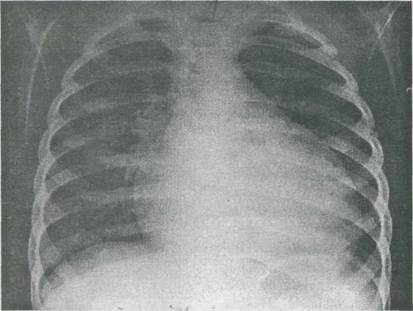

Examenele paraclinica Radiografia cardio-pulmonara - evidentiaza cardiomegalie globala, constanta si importanta, uneori cu ventriculul stâng marit preferential; se mai poate demonstra staza pulmonara si dilatarea arterei pulmonare în caz de hipertensiune arteriala pulmonara.

Fig. 9-20. Cardiomiopatie dilatativa. Radiografia cardiopulmonara evidentiaza cardiomegalie importanta cu hipertrofie mare ventriculara st nga